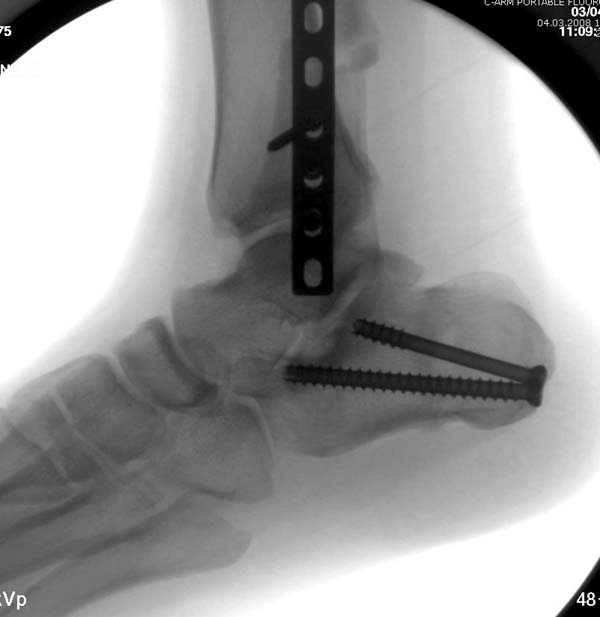

Здесь представлено решение похожей проблемы. Больной в течение года

лечился консервативными мерами, и боли в голеностопе были основным

показанием к операции.

Проведена обычная стандартная процедура по исправлению

неудовлетворительного состояния голеностопного сустава, где кроме

удлинения малоберцовой с применением compression tension device за

проксимальный конец пластины, проведено замещение трикортикальным

графтом из крыла, освобождение синдесмоза и медиальной щели от

фибротических масс с фиксацией.